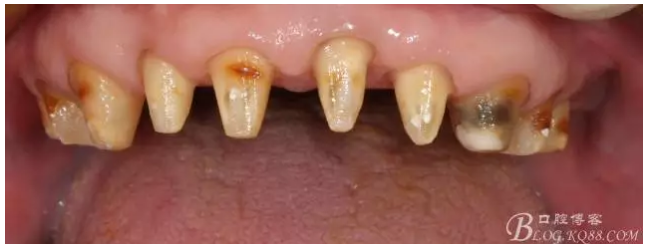

早期的病歷大約在2009年左右,那時(shí)只做了下頜的套筒冠

當(dāng)時(shí)勸病人上頜也做了修復(fù),但是病人感覺這樣還可以,把下面牙齒鑲好再說,雖然上面的牙齒不同程度的牙齦萎縮,都有些松動(dòng),但是患者年歲已高,只做下頜修復(fù)。囑咐病人半年復(fù)診一次,可是病人這一走就是2年,來要求制作上牙的修復(fù)

上牙出現(xiàn)了不同程度的牙齦萎縮